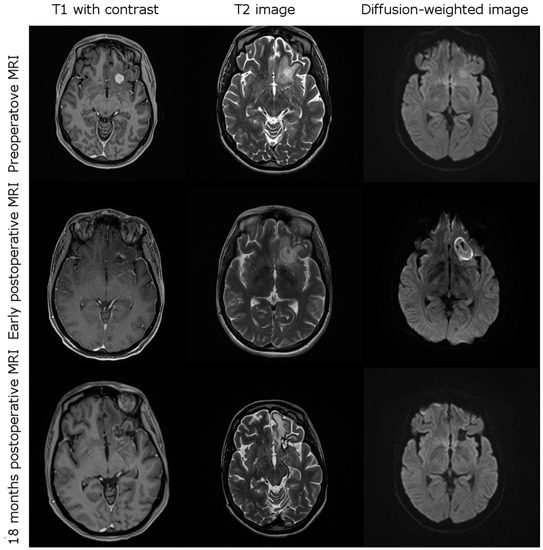

3.3. Imging after iPDT